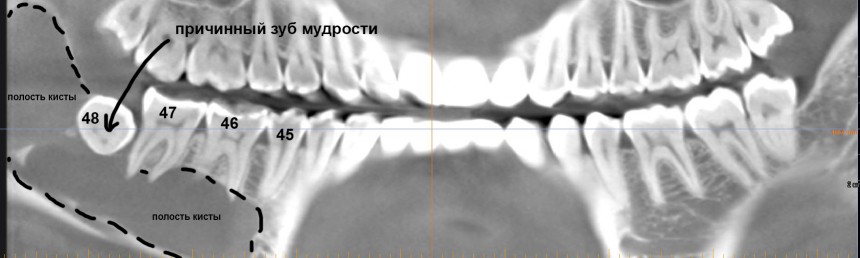

Для тех, кто не разбирается в компьютерной томографии, я поясняю:

Как видите, большую часть тела и ветви нижней челюсти справа занимает гигантская фолликулярная киста. Она образовалась из-за ретинированного зуба мудрости #48. Дело в том, что вокруг ретинированных зубов мудрости сохраняется фолликул, оболочка зачатка зуба. И в определенных условиях (каких — науке пока неизвестно) клетки фолликула могут пойти в рост — он постепенно вытесняет костную ткань и формирует гигантские кисты, которые называются фолликулярными.

Что вообще делать в таких случаях? Проблемный зуб — удалять. Кисту, разумеется, тоже удалять. Но прежде нужно внимательно изучить клиническую ситуацию и кое-как подготовиться к операции.

- Полость кисты очень большая, переходит с тела на ветвь нижней челюсти. Проблема решаема правильным доступом.

- Где-то на дне полости кисты находится нижнелуночковый нерв (на картинке ниже выделен красным). У пациентки пока нет парестезии, это дает основания предполагать, что нервный ствол не поврежден и располагается за пределами полости кисты. Нужно соблюдать осторожность и, на всякий случай, предупредить пациентку о возможном возникновении парестезии после операции.

- Из-за больших объемов полости, у тела и ветви нижней челюсти остались очень тонкие костные стенки. И, даже если мы удалим кисту через относительно небольшой доступ, мы этим самым доступом ослабим и без того невысокую прочность нижней челюсти. Может случиться перелом даже во время зевка. Поэтому следует подумать о каком-то армировании или укреплении раны после операции. Запасаемся титановыми минипластинами и винтами.

- 46 и 47 зубы проникают в полость кисты, электроодонтодиагностика показывает высокие значения (некроз пульпы). Следовательно, если оставить эти зубки с пульпой, останется риск рецидива кисты уже из-за этих зубов. Их нужно депульпировать — и это главная предоперационная подготовка их депульпированием занимается врач-терапевт.

- Из опыта предыдущих операций я знаю, что нередко оболочка кисты образует спайки с корнями зубов, поэтому очень сложно от них отделяется. Нужно быть готовым на расширение доступа и резекцию верхушек корней 46 и 47 зубов.